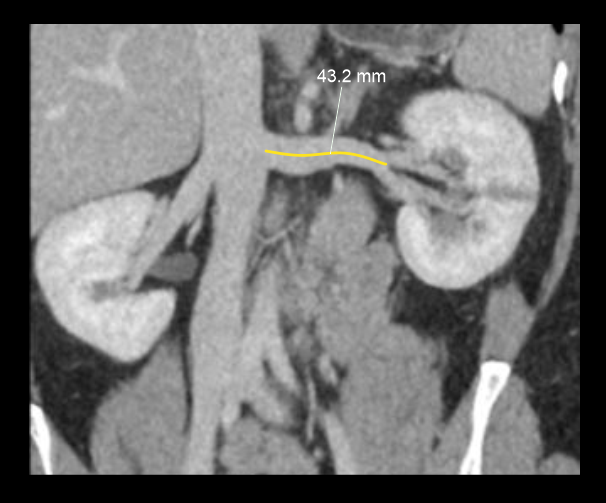

- Kidney size measurement in MPR images (Nephrographic phase).

- Renal artery pre-hilar arterial branching distance measurements on curved MPR or on 3D images, separately for both renal arteries.

- Renal artery diameter measurements from abdominal aorta to first branching on proximal, mid and distal points.